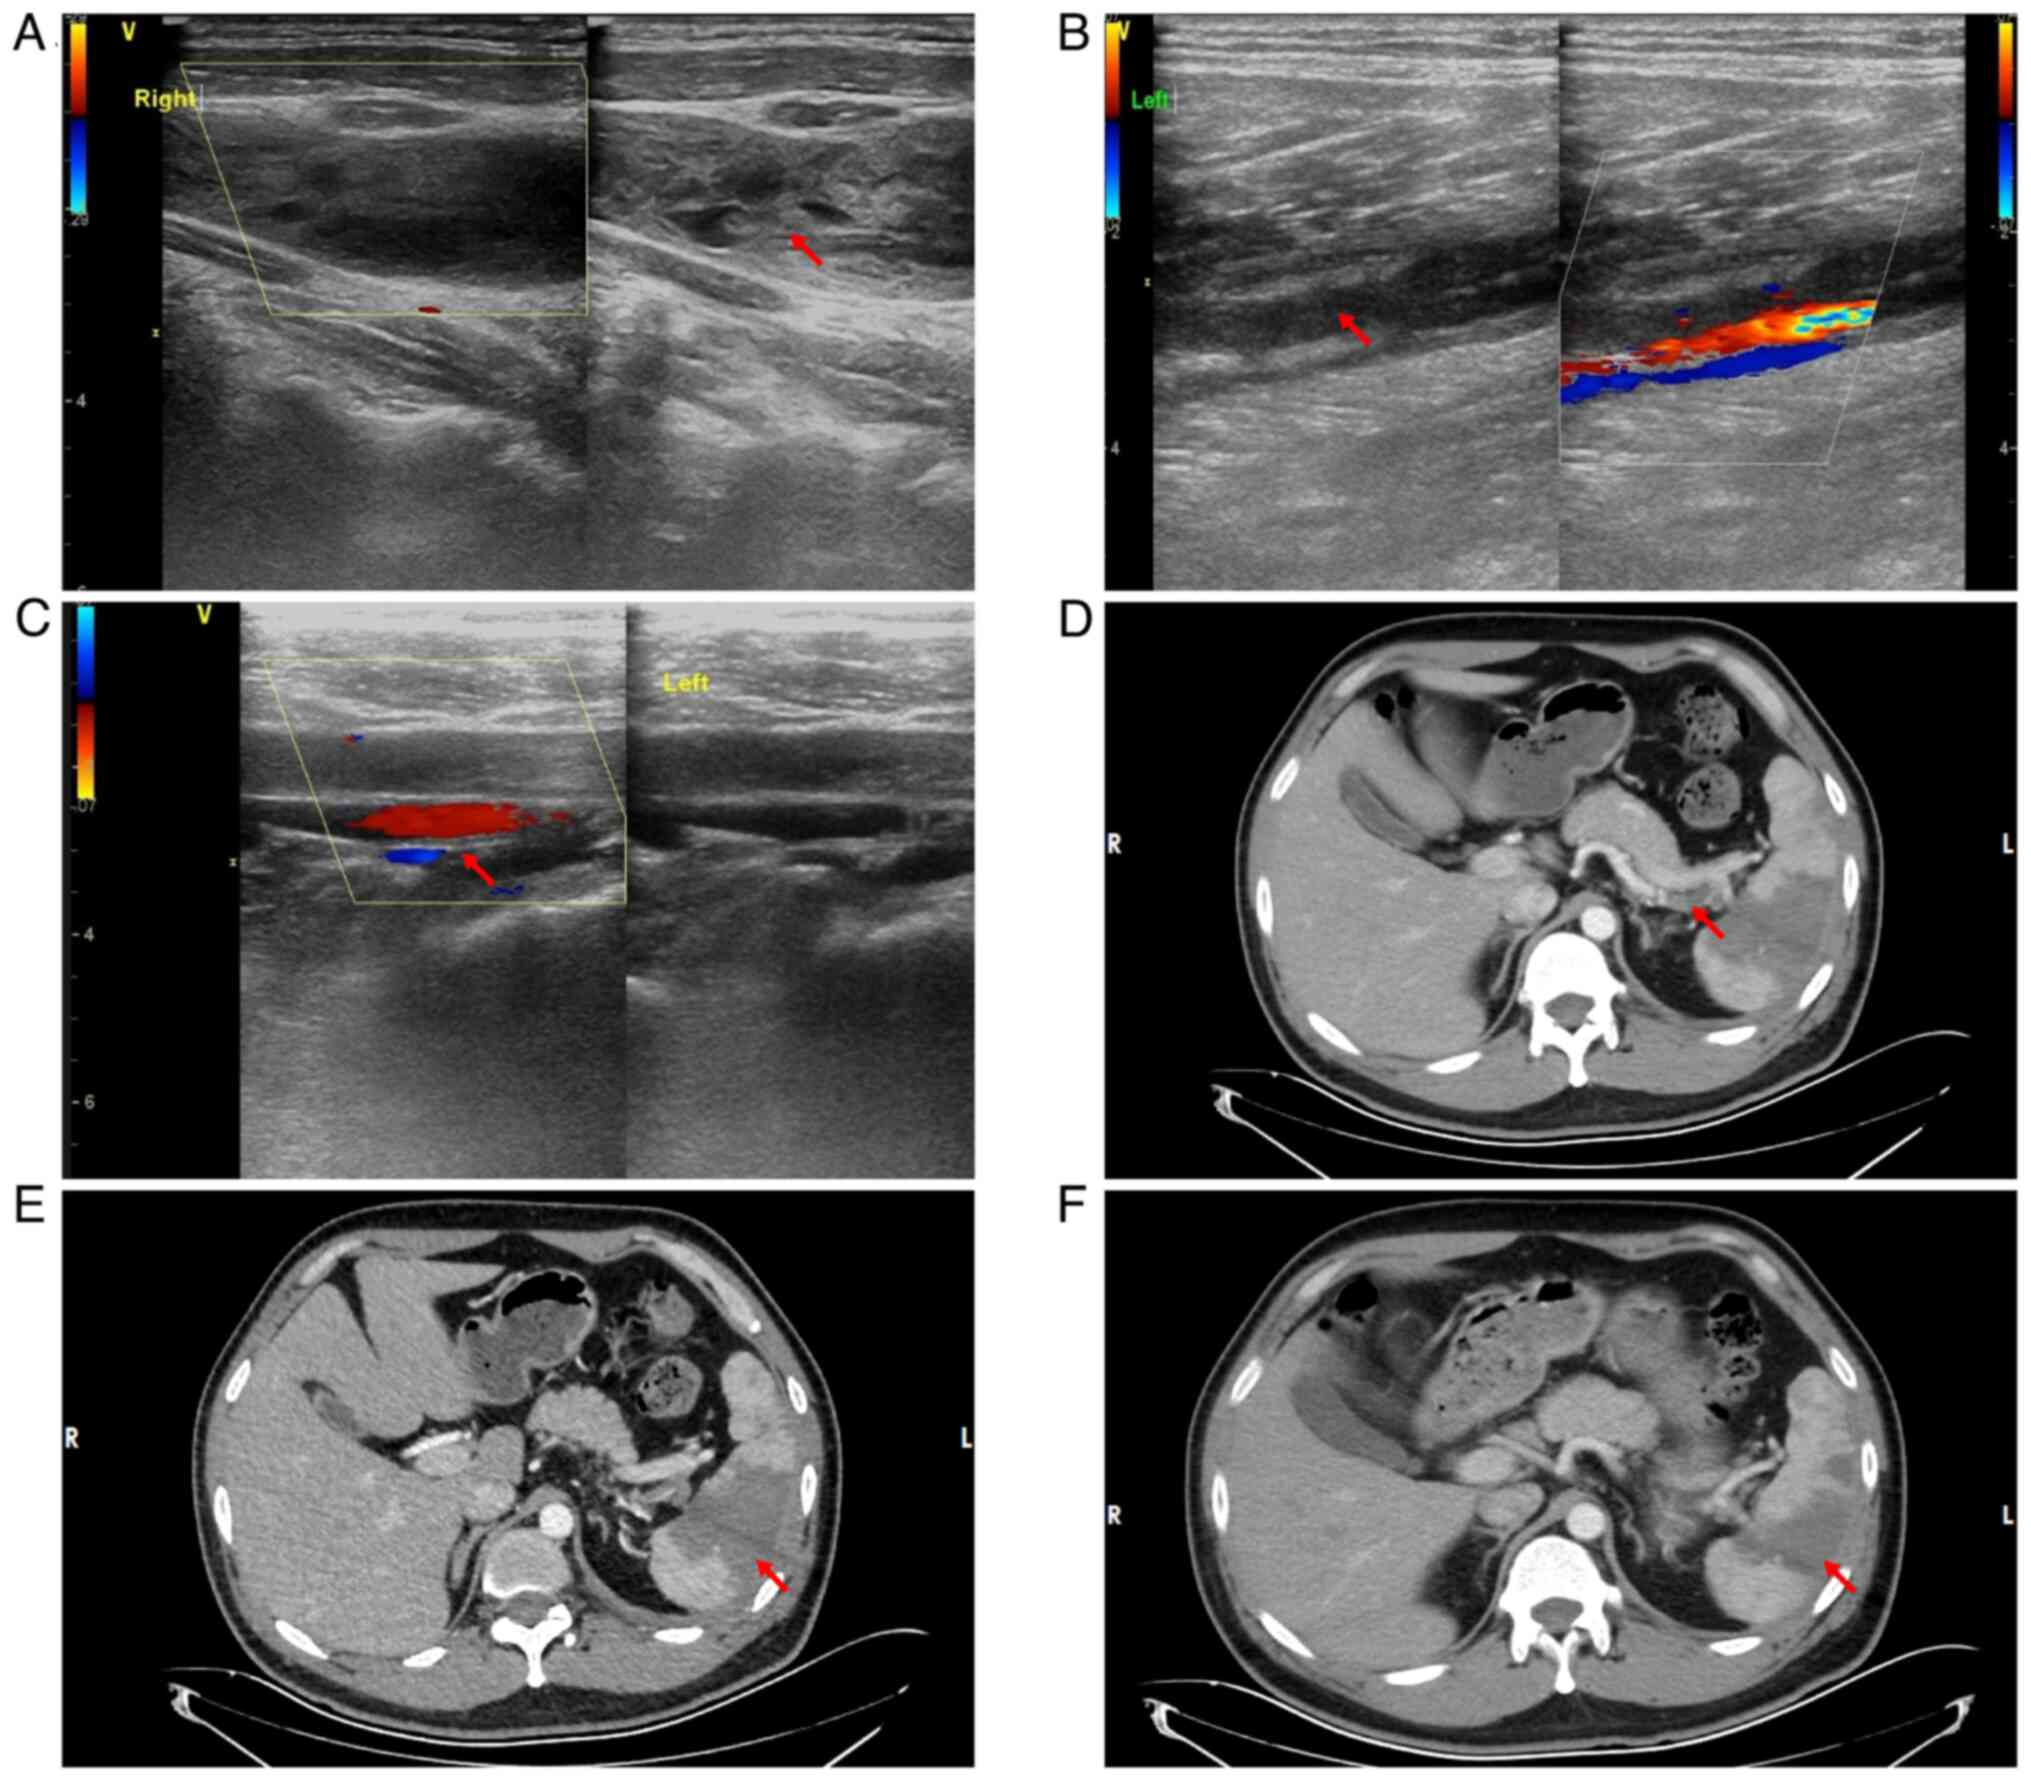

Complementary vascular ultrasonography (December 2023) demonstrated extensive thromboembolic disease: Acute thrombosis included the distal left superficial femoral vein, popliteal vein, right internal jugular vein and bilateral posterior tibial/peroneal veins, with venostasis evident in the remaining lower extremity vasculature. Cervical venous evaluation identified aneurysmal dilatation of the right internal jugular vein containing intraluminal thrombus (Fig. 3A-C). Contrast-enhanced abdominal CT demonstrated a filling defect and hypodense intraluminal shadow within the splenic artery distal to the pancreatic body segment (Fig. 3D). Concomitant absence of parenchymal enhancement in a portion of the spleen confirmed the diagnosis of splenic artery embolism with resultant splenic infarction (Fig. 3E).

Ultrasound findings indicating

multiple thrombi formation in multiple locations and

contrast-enhanced abdominal CT revealing splenic infarction. A

colored scale is used to indicate the direction and relative

velocity of the blood flow signal, with red indicating blood flow

towards the ultrasound probe and blue indicating blood flow away

from the ultrasound probe. (A) Color Doppler ultrasound indicated

thrombosis in the right internal jugular vein. The red arrow

indicates a thrombosis. (B) Color Doppler ultrasound demonstrated

thrombosis in the left popliteal vein. The red arrow indicates a

thrombosis. (C) Color Doppler ultrasound indicated thrombosis in

the left peroneal vein. The red arrow indicates a thrombosis. (D)

Contrast-enhanced abdominal CT demonstrated splenic artery

thrombosis and the red arrow indicates the thrombus. (E)

Contrast-enhanced CT demonstrated wedge-shaped hypodensity in the

splenic parenchyma, indicated by the red arrow, consistent with

ischemic infarction. No evidence of liquefactive necrosis or

abscess formation was observed. (F) Following a standard

anticoagulation regimen (8,000 IU subcutaneously every 12 h), at 1

month post-treatment, contrast-enhanced CT revealed a slight

reduction in the extent of the splenic infarction. The red arrow

indicates the infarcted spleen.

Figure 3.

Ultrasound findings indicating multiple thrombi formation in multiple locations and contrast-enhanced abdominal CT revealing splenic infarction. A colored scale is used to indicate the direction and relative velocity of the blood flow signal, with red indicating blood flow towards the ultrasound probe and blue indicating blood flow away from the ultrasound probe. (A) Color Doppler ultrasound indicated thrombosis in the right internal jugular vein. The red arrow indicates a thrombosis. (B) Color Doppler ultrasound demonstrated thrombosis in the left popliteal vein. The red arrow indicates a thrombosis. (C) Color Doppler ultrasound indicated thrombosis in the left peroneal vein. The red arrow indicates a thrombosis. (D) Contrast-enhanced abdominal CT demonstrated splenic artery thrombosis and the red arrow indicates the thrombus. (E) Contrast-enhanced CT demonstrated wedge-shaped hypodensity in the splenic parenchyma, indicated by the red arrow, consistent with ischemic infarction. No evidence of liquefactive necrosis or abscess formation was observed. (F) Following a standard anticoagulation regimen (8,000 IU subcutaneously every 12 h), at 1 month post-treatment, contrast-enhanced CT revealed a slight reduction in the extent of the splenic infarction. The red arrow indicates the infarcted spleen.

Abdominal CT

Contrast-enhanced abdominal imaging demonstrated persistent non-enhancement of splenic parenchyma consistent with established infarction. Comparative volumetric analysis indicated interval reduction (23.4%) in the infarcted volume compared with the baseline (December 2024; Fig. 3D and E), which suggested partial splenic reperfusion (Fig. 3F).

Ultrasound of neck veins

Color Doppler ultrasonography identified a persistent non-occlusive thrombus within the right internal jugular vein (data not shown), unchanged from prior examinations (Fig. 3A).